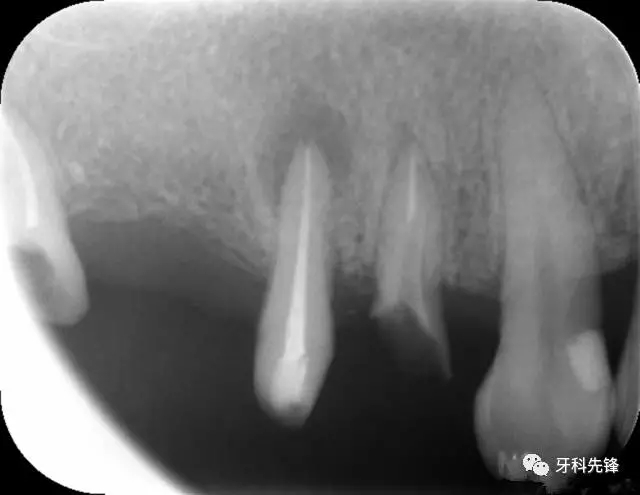

圖8治療術(shù)后X光片

640.webp (10).jpg

640.webp (11).jpg

640.webp (12).jpg

圖18 14  15   三個月后X光片(根尖陰影減?。?/p>

640.webp (22).jpg